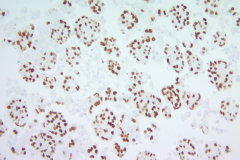

Immunohistochemistry (IHC) stains can also be an important tool in proper diagnosis of EHE. Stains such as CD31, CD34, and ERG have been described to stain EHE.2,3 CD31 is a platelet endothelial cell marker expressed frequently in vascular endothelial cells. CD34 stains for 90% of vascular tumors because it is a highly glycosylated transmembrane glycoprotein associated with the origin of vascular tumors. Positive staining for both CD31 and CD34 is considered diagnostic of this tumor.1 In this case, we have CAMTA1, a tumor suppressor transcription factor, staining positively for EHE shown in Image 1.